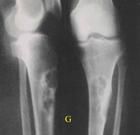

X線顯示病變呈單房性或多房性囊性透亮區,透亮區內可見鈣化斑塊狀陰影。骨皮質內偏心性溶骨性破壞,皮質骨膨脹、變薄,髓腔變窄、邊緣硬化。發生於脛骨時可見前方骨皮質有膨脹性透亮病損,邊緣清晰,很少骨膜反應。少見脛骨多發病變或侵入大部骨幹。